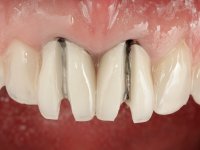

Paciente do sexo feminino com 41 anos de idade, não fumadora. Apresentava duas coroas sobre espigões falsos cotos fundidos nos dentes 1.1 e 2.1. As coroas apresentavam-se com infiltrações cervicais com exposição da superfície radicular. A papila gengival mediana, apresentava-se ligeiramente retraída. O espaço mesio-distal correspondente às duas coroas mostrava-se alto e estreito. Apresentava um ligeiro apinhamento dos incisivos inferiores, bem como uma pequena retração gengival. No sorriso era bem visível a zona cervical das coroas, mostrando um aspeto acinzentado correspondendo ao escurecimento radicular. No exame imagiológico verificou-se que o tratamento endodôntico não estava tecnicamente satisfatório, mas assintomático à quase 10 anos.

O tratamento iniciou-se com a confeção de moldeiras transparentes em silicone para aplicação de peróxido de carbamida a 16%. Os espaçadores colocados na superfície vestibular foram cuidadosamente preparados em resina nos modelos de gesso. O tratamento foi feito aplicando o produto 2 horas por dia durante 8 dias. Após o branqueamento esperamos 4 semanas e iniciamos o tratamento prostodôntico. Foi realizada uma pré-impressão em silicone para confeção de uma ponte provisória com resina composta de polimerização dual. Em seguida iniciamos a remoção das coroas. Foi feito um corte vertical na zona média da coroa até encontrar a superfície do espigão falso coto fundido. No bordo incisal também foi realizado o mesmo corte. Em seguida com um luxador fino foi feita a separação das partes distais das coroas. Para a remoção das partes mesiais foi feito um corte na linha média abrangendo ambas as coroas. No final da remoção atraumática das coroas antigas os cotos foram re -preparados. Na re-preparação dos cotos a linha de acabamento foi colocada a nível intra-sulcular. Na mesma consulta foi feita a impressão definitiva. O afastamento gengival foi realizado com a técnica da pasta de caolino comprimida pela ponte provisória.  A impressão foi feita pela técnica de dupla mistura com dupla viscosidade com silicone de presa rápida. No laboratório foram confecionadas 2 coroas com infraestrutura em Zr sendo revestidas a cerâmica. No sentido de evitar aparência de coroas “muito altas” foi aumentado ligeiramente o diâmetro mesio-distal sobrepondo-se ligeiramente aos dentes adjacentes. A ponte provisória foi removida os cotos foram polidos e as coroas foram colocadas para verificação final. Confirmado o seu ajuste e aprovadas pela paciente foram cimentadas definitivamente com cimento de ionómero de vidro reforçado com resina.